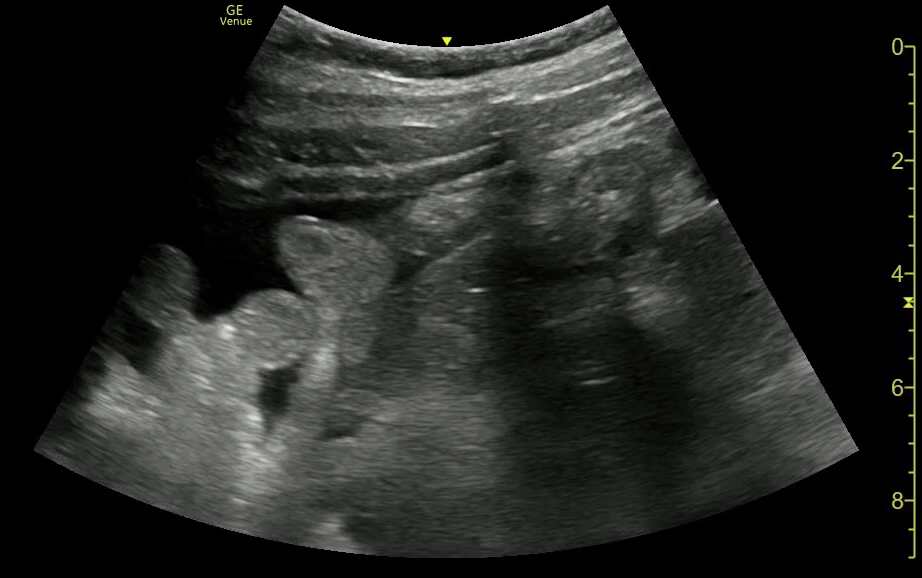

Prox Ureteral Stone, Sponge Kidney